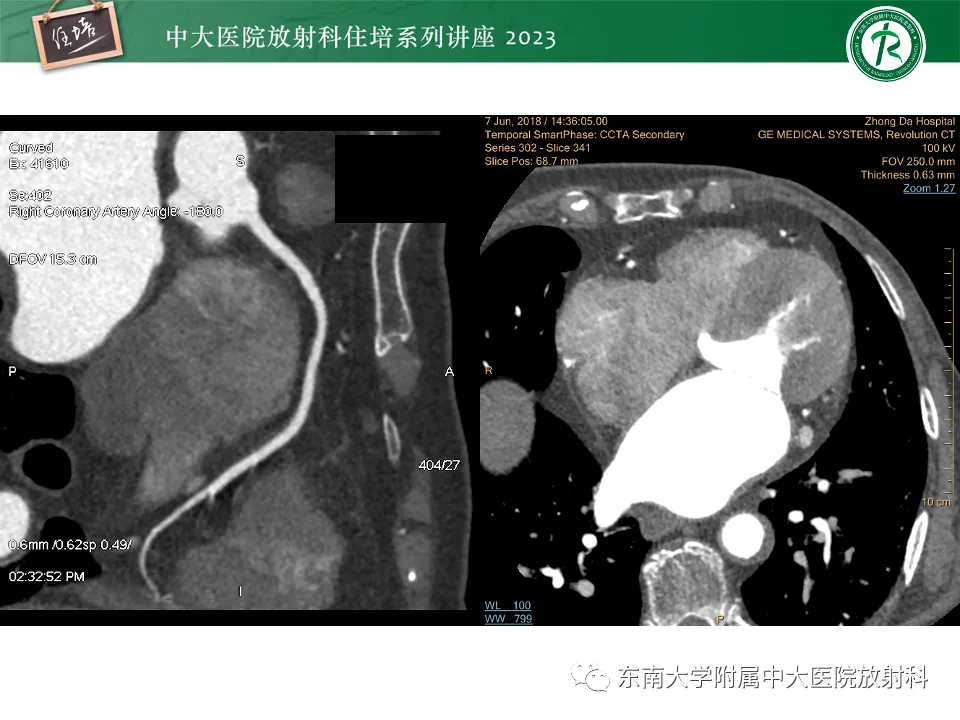

>精美课件丨心脏大血管常见疾病CT图像后处理要点

精美课件丨心脏大血管常见疾病CT图像后处理要点

来源:东南大学附属中大医院医学影像科